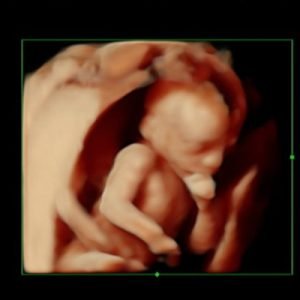

3D Υπερηχογράφημα

Επιπλέον, θα πραγματοποιήσει, στον κατάλληλο χρόνο, την υπερηχογραφική εξέταση β επιπέδου. Στο 3ο τρίμηνο της κύησης, θα διενεργήσει την εξέταση Doppler.